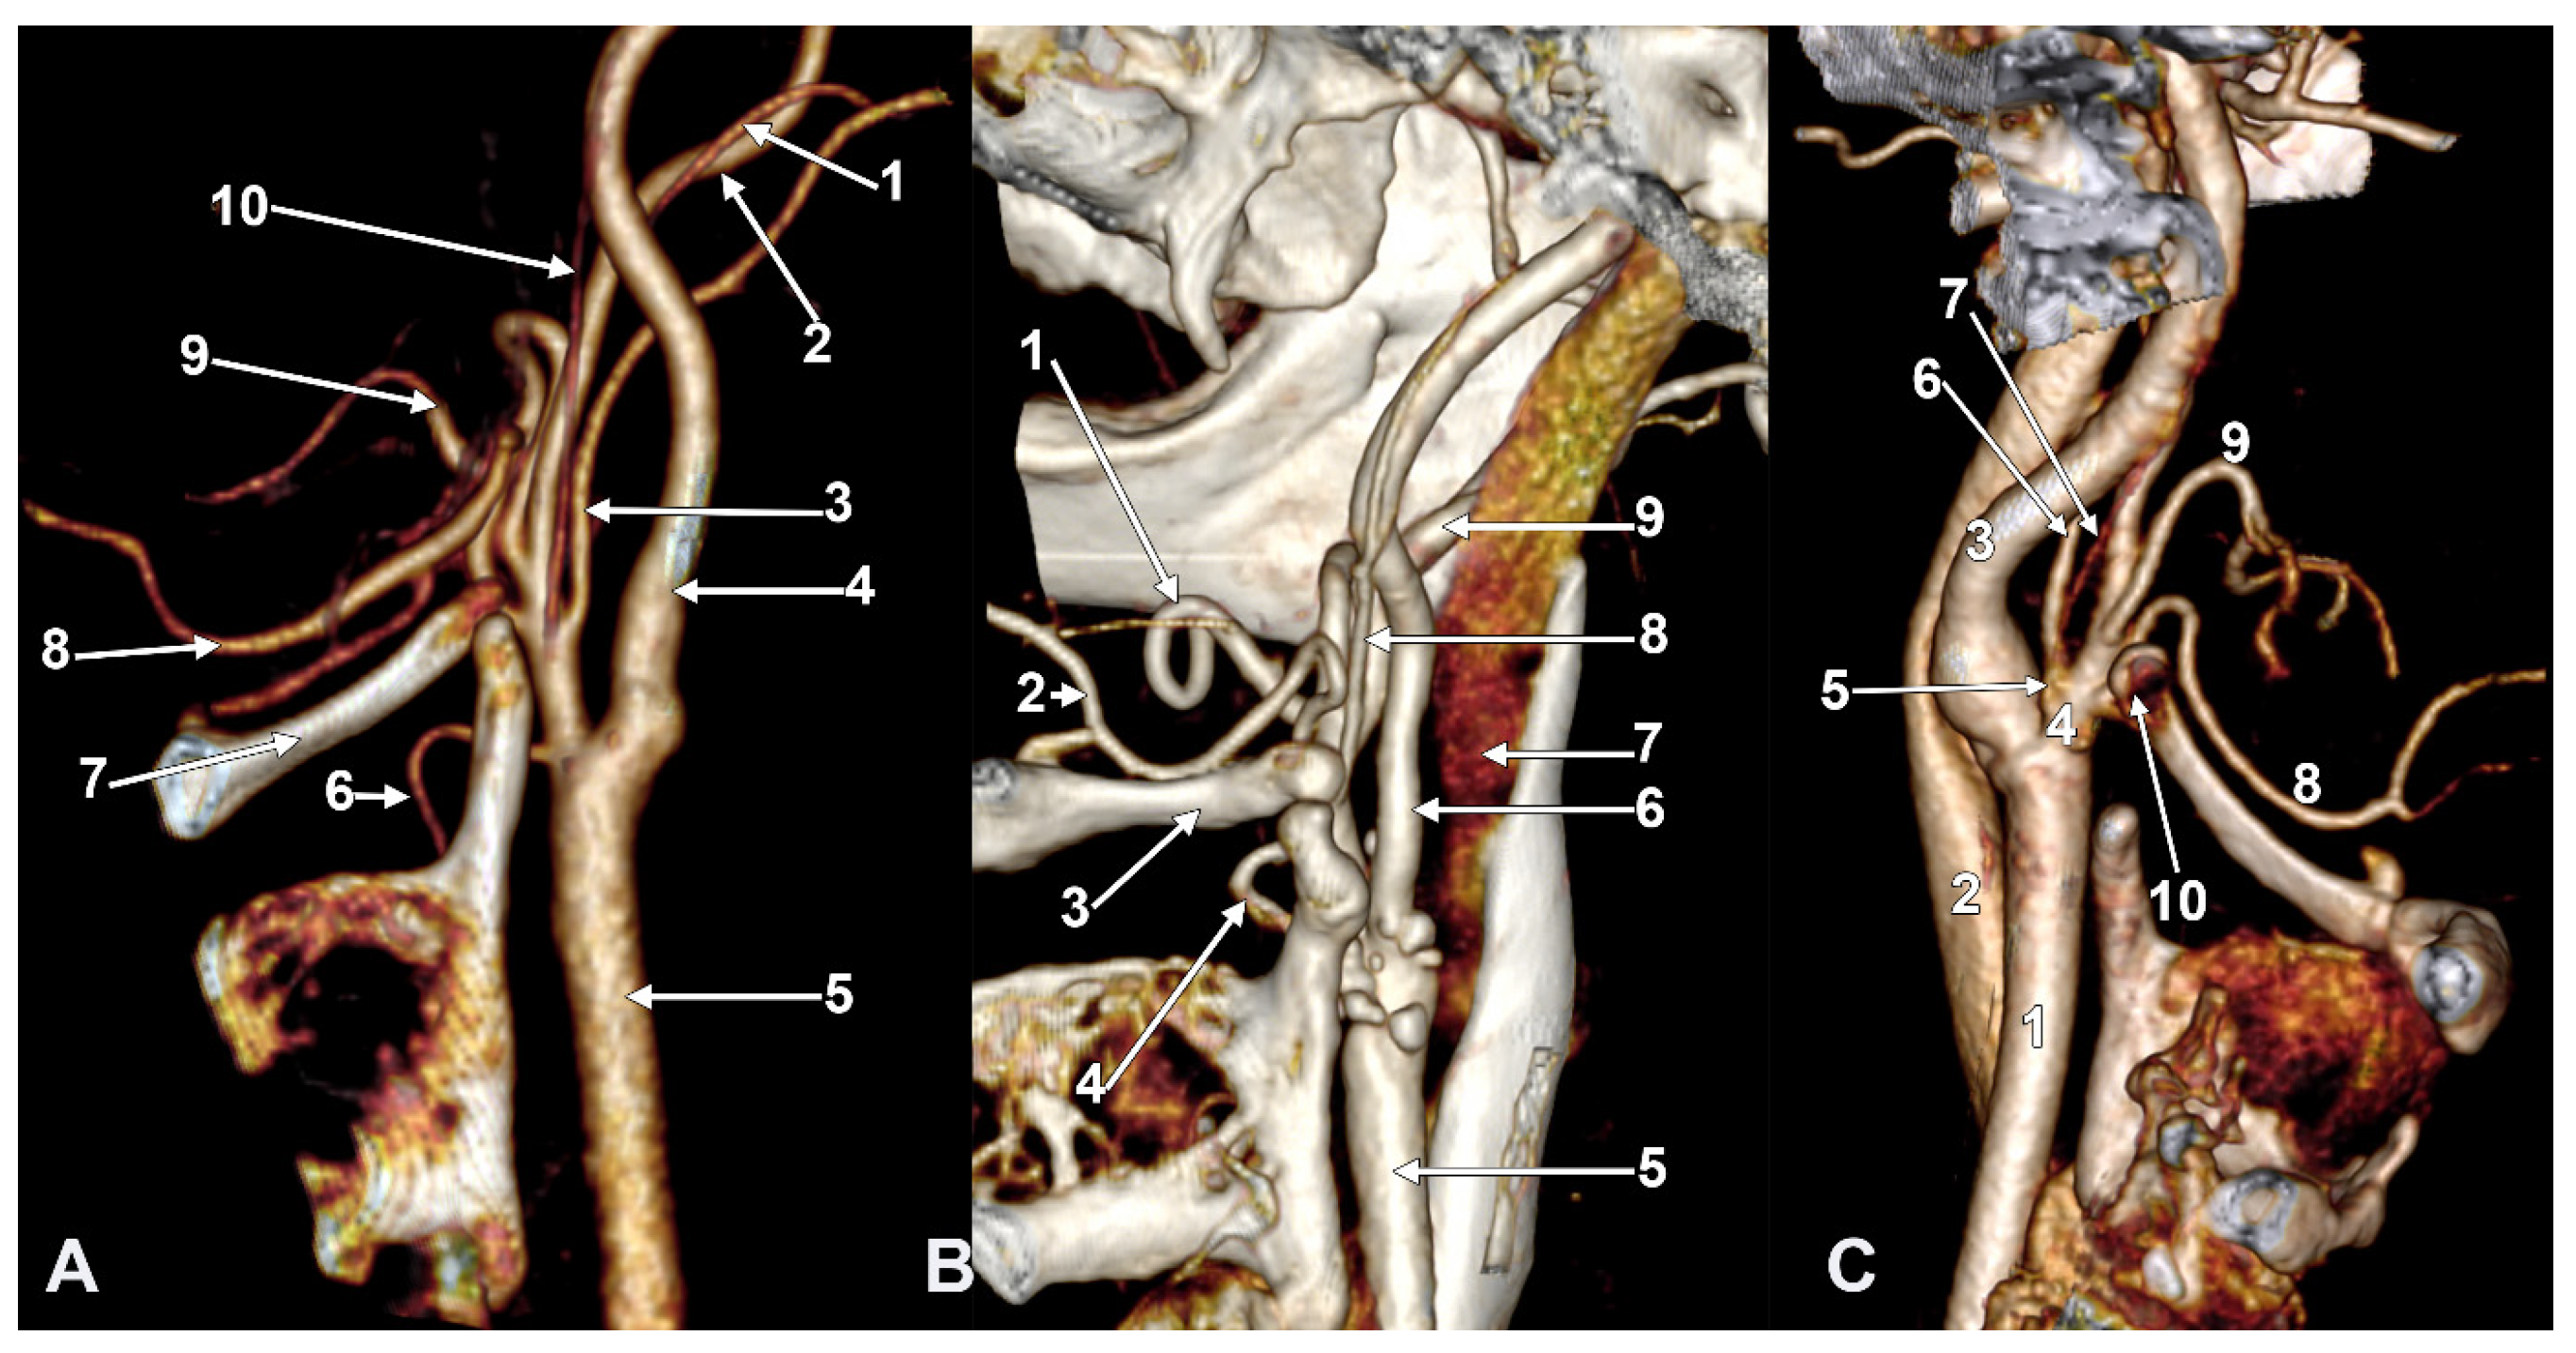

Figure 9. Thyrolingual trunk originating from the common carotid artery. The ascending pharyngeal artery is the first branch of the external carotid artery. Type 33 of the sequence of branches of the external carotid artery. Three-dimensional rendering. Left side. (A) Posteromedial view. (B) Antero-lateral view. 1. Common carotid artery; 2. greater hyoid horn; 3. thyrolingual trunk; 4. internal carotid artery; 5. ascending pharyngeal artery; 6. external carotid artery; 7. superior thyroid artery; 8. lingual artery; 9. facial artery; 10. styloid process; 11. ossified stylohyoid ligament.

On the left side (Figure 9), the APA originated 8.9 mm posterosuperior to the tip of the greater hyoid horn from the posterior wall of the origin of the ECA, as its first branch. This was because the LA and STA arose via a common TLT from the CCA. The TLT origin was 8.8 mm inferior to the greater hyoid horn; the length of this common arterial trunk was 5.1 mm. It divided at 5 mm lateral to the superior horn of the thyroid cartilage into two vertical branches—an upper one, the LA, which ascended over the greater hyoid horn and made an upper loop before continuing with the hyoglossal segment, and a second, inferior one, the STA.